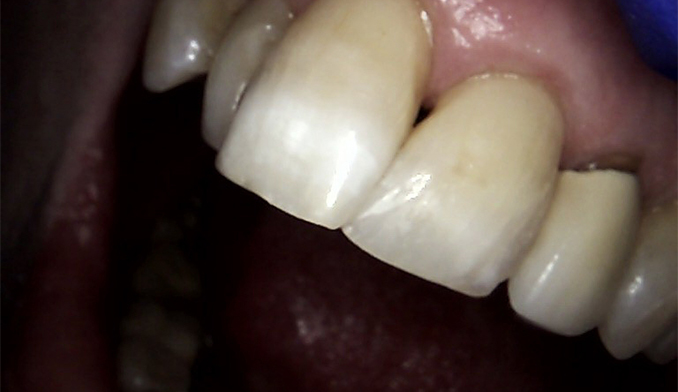

Front Tooth Repair with Bonding

The patient fractured her front tooth. We restored both the appearance and function of the tooth using cosmetic bonding, achieving a natural-looking and durable result.